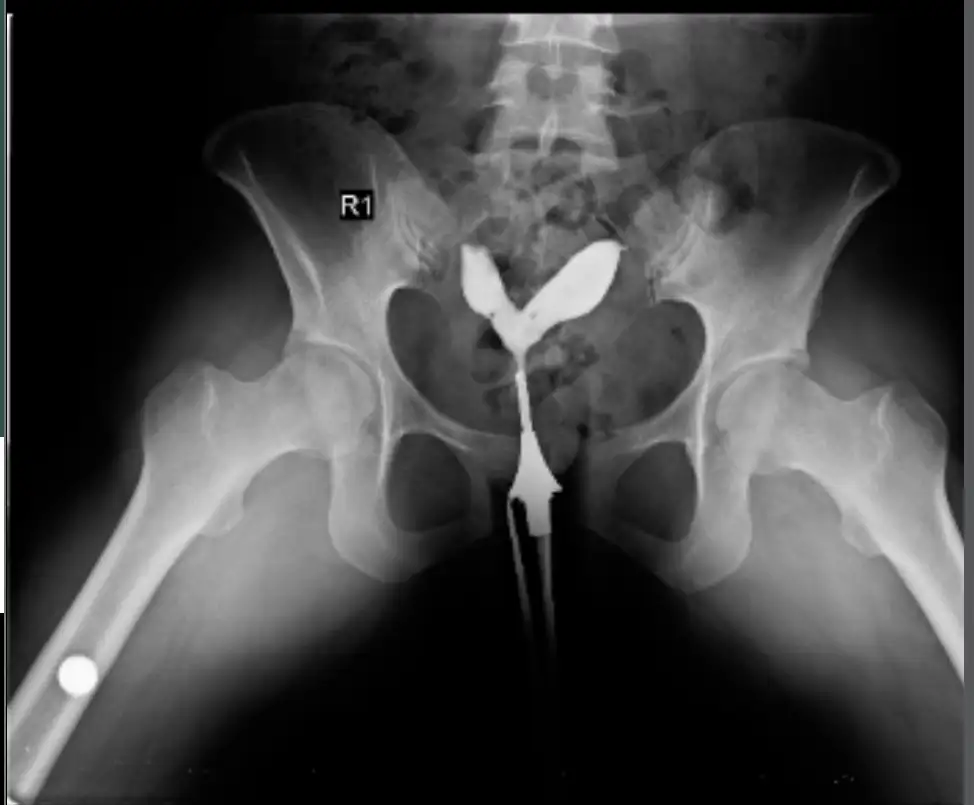

Hsg sonuç raporumda bu yazıyor bilen var mi ne bu 😭

Canım rahim nerede tüpler nerede ... valla ben benimkini araştırırken baya baya anlar olmuştum ama filminde başka foto yok mu? İlk çekimleridir belki yani daha sıvıyı tam göndermedikleri anın fotolarıdır bunlar

canım bu çıktı raporumda ne yazmışlar bu ne demek anlıyor musun ?

Canım sıvıyı verdiklerinde kanallarda dolaştı ya soldaki sağa göre daha hızlı gelmiş ama gelmiş yani. Hafif tıkanıklık olmuştur o da açılmıştır sorun yok gibi duruyor

Hadi inşallah Allah razı olsun , kaç gündür kafamda kuruyordum. Belki de ilaç sayesinde açıldı 🙏🏻 ☺️ Hiç bir sorun görünmemişti eşimde de ben de de yaşım 35 hiç çocuğum olmadı 1,5 yıldır çocuk düşünüyoruz son çare tüp bebek , tüp bebekten önce rahim filmi demişti doktor , benim çok canım yanmıştı hsg de 3 gün kendime gelemedim dengem alt üst oldu demek ki tıkanıklık varmış ondan çok zor geçmiş benim ki